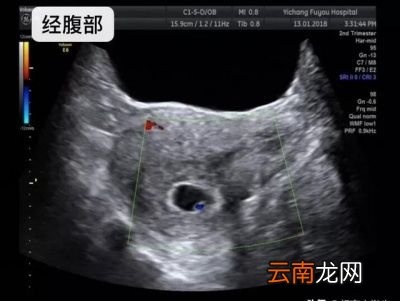

做经腹部彩超不好吗?虽然经腹部彩超也可以看,但是首选要憋尿,对于普通人来讲憋尿可能不是很难 。但是怀孕以后,子宫增大,本身就会压迫膀胱,让孕妇尿意十分敏感,如果这个时候让孕妇憋尿,就会更困难了 。可是膀胱不充盈,加上本身腹部脂肪、腹腔肠道气体的干扰,就更不容易观察孕囊的情况了 。

哪种情况,推荐经腹部彩超?如果孕妈首次去医院产检打算做彩超的时候已经有些晚了,在平时月经周期也正常的情况下,首次检查时间怀孕超过50+天,就可以做经腹部妇科超声检查孕囊的情况,这个时候只是需要稍微憋尿就可以了 。